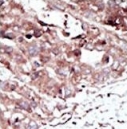

IHC testing of FFPE human cancer tissue with PHKG2 antibody. HIER: steam section in pH6 citrate buffer for 20 min and allow to cool prior to staining.

Immunohistochemistry (FFPE) : 1:50-1:100